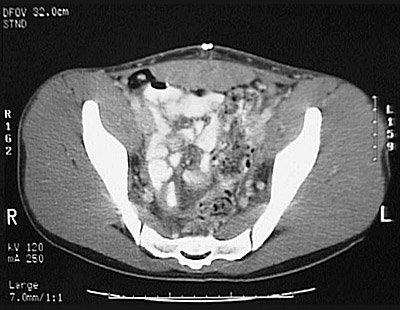

[S3] This is a normal pelvic CT scan with contrast demonstrating the colon and right ilium and left ilium and loops of small intestine and iliacus muscle and gluteus medius muscle and gluteus maximus muscle and gluteus minimus muscle and right sacroiliac joint and sacrum and left sacroiliac joint and rectum in the pelvis.